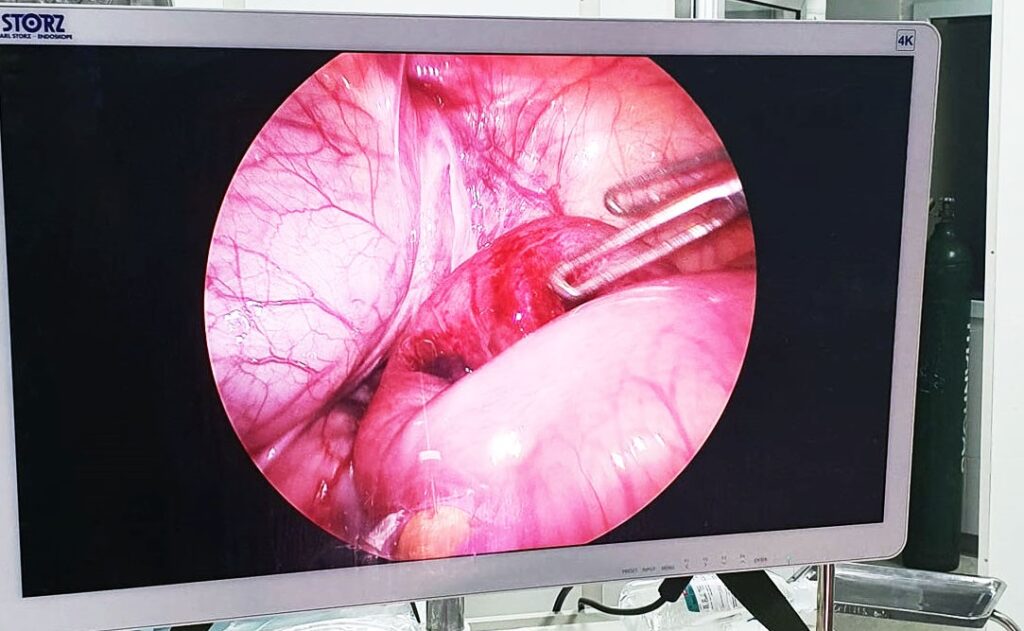

Qua khai thác và thăm khám lâm sàng, các bác sĩ chẩn đoán trẻ bị thoát vị bẹn nghẹt bên phải. Ngay lập tức kíp cấp cứu khẩn trương chuyển bé lên phòng mổ nội soi cấp cứu, kịp thời đưa khối thoát vị là một đoạn ruột non dài 08cm ra khỏi ống bẹn, sau 5 phút đoạn ruột đã được cung cấp máu và hồng trở lại, tránh được tình trạng dẫn đến hoại tử ruột. Sau mổ, sức khỏe trẻ dần ổn định và đã được ra viện.